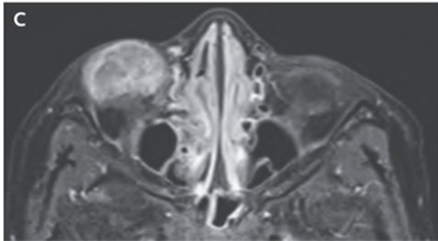

MRI施行。→眼球の前下部分に沿って不均一で境界明瞭のT1低信号、T2高信号の腫瘤が確認された。